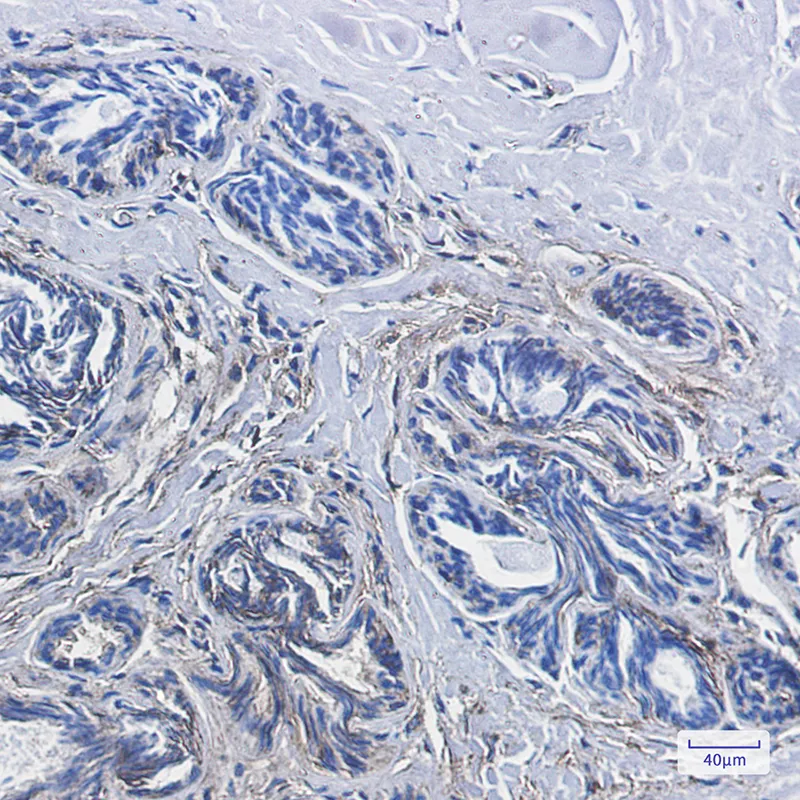

CD99 Rabbit Monoclonal Antibody

Cat: AMRe01801

Size1:50μL Price1:$158

Size2:100μL Price2:$288

Size3:500μL Price3:$1200

Application:WB,IHC-P,IP

Reactivity:Human,Mouse

Conjugate:Unconjugated

Gene Name:CD99

Size2:100μL Price2:$288

Size3:500μL Price3:$1200

Application:WB,IHC-P,IP

Reactivity:Human,Mouse

Conjugate:Unconjugated

Gene Name:CD99